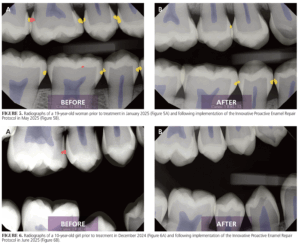

In 2024, I documented outcomes directly attributable to IPERP (Figures 5 and 6). Treatment acceptance reached 95%, driven by the clarity of diagnostic visuals and the simplicity of the noninvasive intervention. IPERP has easily integrated into our existing workflows and allowed us to be more efficient, without auxiliary staff involvement or additional chair time.